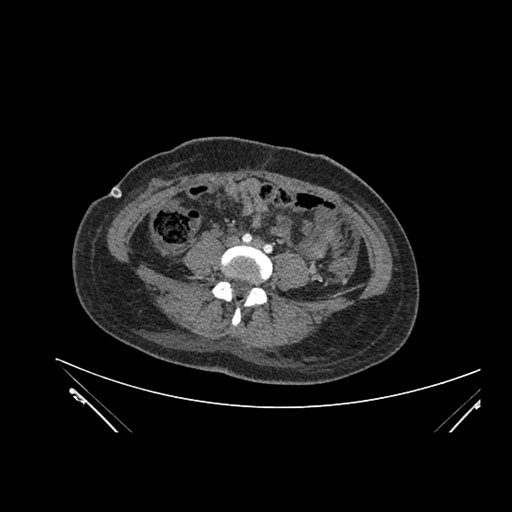

Axial Arterial

Axial Venous

Imaging analysis

Based on initial findings, which issue(s) would you be most concerned about?